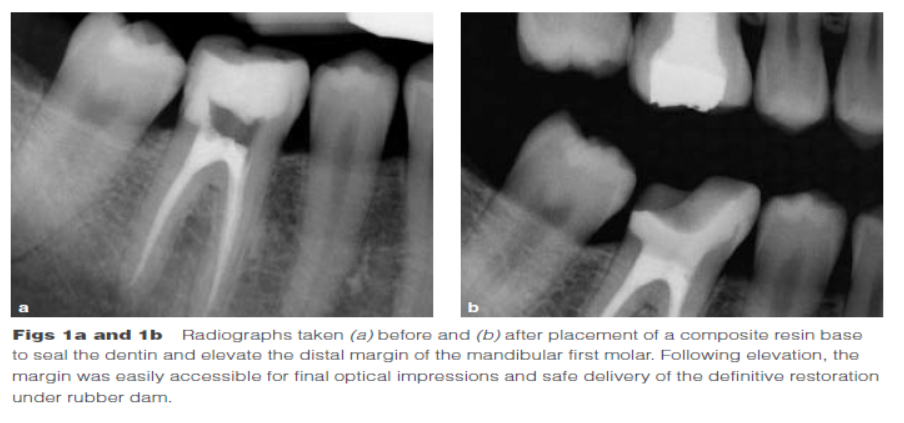

Dietschi和Spreafico在1998年提出了另一種方法,即在間接修復(fù)體的下面放置一個復(fù)合樹脂基底來取代冠向提升邊緣(圖1)。這個方法即我們所知的齦壁提升術(shù)(DMG)是在橡皮障隔離下完成的?(This procedure,…,is performed under rubber dam isolation following the placement of a matrix.)如今,DME(齦壁提升術(shù))通常與IDS(即刻牙本質(zhì)封閉術(shù))聯(lián)合使用來促進(jìn)間接粘接修復(fù)體的粘接和齦邊緣的封閉。此外,邊緣的齦上提升,粘接復(fù)合樹脂基底被用于封閉牙本質(zhì)、加強(qiáng)潛在牙尖?(reinforce undermined cusps),充填倒凹(fill undercuts),以及為嵌體/高嵌體修復(fù)提供必要的幾何形態(tài)。

DME是用一個改良彎曲的成型片接堆放復(fù)合樹脂來提升齦壁高度,使其能夠在修復(fù)過程中使用橡皮障封閉邊緣,可以在固化前適當(dāng)?shù)囊瞥嘤嗟膹?fù)合樹脂。DME應(yīng)該在即刻牙本質(zhì)封閉(IDS)之后,在使用橡皮障的條件下,且僅在邊緣可被改良的成型片適當(dāng)隔離時直接獲得。否則,這個技術(shù)不能使用。在最終取印前,需要拍攝咬合翼片來評估復(fù)合樹脂在齦邊緣區(qū)域的密合度(有無懸突或缺陷)。同樣需要仔細(xì)隨訪來評估軟組織的健康和是否需要外科手術(shù)干預(yù)。只要可能,在牙髓治療前就應(yīng)通過DME術(shù)制造假壁,使根管治療更完善(圖2、3)。圖4展示了一個典型DME術(shù)的適應(yīng)癥。